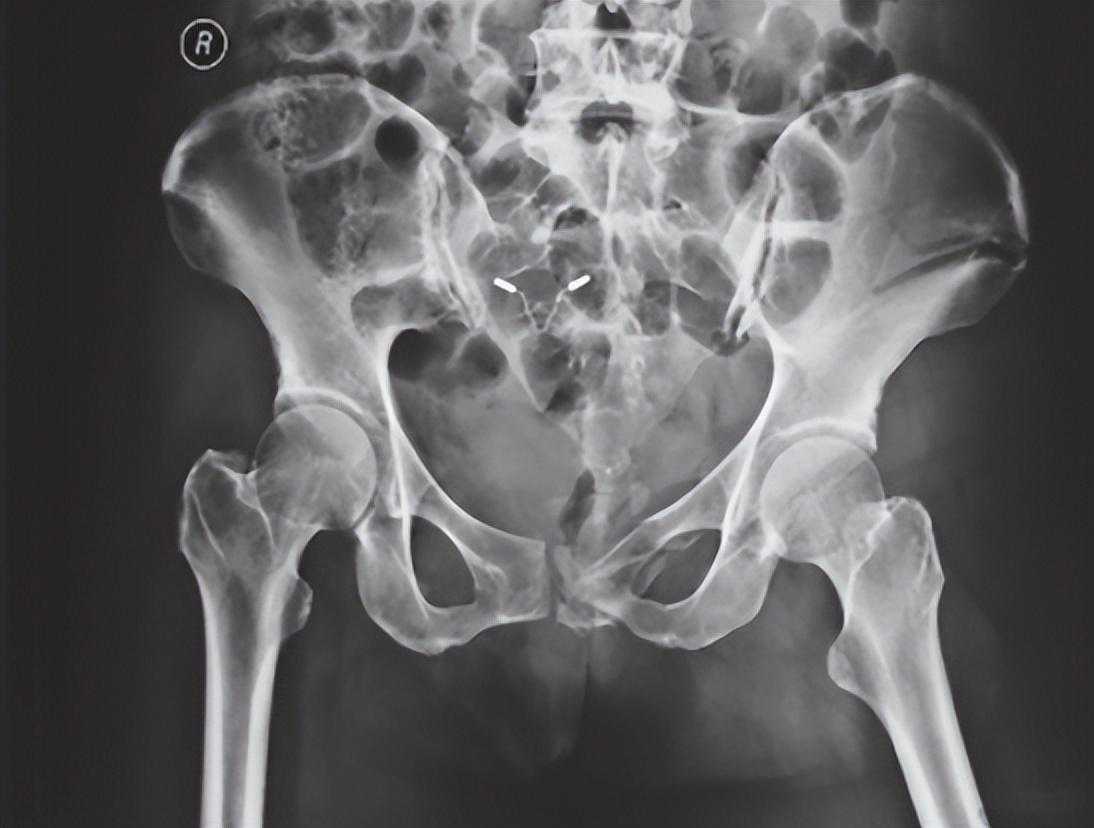

图7骨盆后环损伤X线片可见耻骨联合分离、耻骨支骨折,提示骨盆前环损伤;髂骨骨折、骶髂关节分离,骶骨骨折,提示后环损伤;L5横突骨折(箭头所示)、骶棘韧带和骶结节韧带撕脱骨折,提示骨盆骨折不稳,移位较大

在压缩型损伤中,骨盆后环损伤侧的髂骨翼向内旋,在X线正位片中,其髂骨翼宽度(测量髋臼上方髋骨或骶髂关节至髂前上棘之间距离)比对侧窄。由于髂骨扭转,其闭孔由斜变正,显得大于对侧,耻骨联合被挤离中线,向对侧移位。伤侧髂骨向上脱位或移位多者可造成耻骨联合上下分离。在分离型损伤中,后环伤侧髂骨翼向外旋,由斜变平,显像宽于对侧,耻骨联合被牵拉离开中线向伤侧移位,或出现耻骨联合分离,外旋髂骨的闭孔更斜,故显像比对侧小。此类骨折损伤严重,常合并休克,手术时需要前后联合入路(图9)。

图9骨盆扭转变形X线片可见右侧耻骨上、下支骨折,耻骨联合分离,右侧骨盆向上移位,提示右侧骨盆后环损伤,向外旋转变形